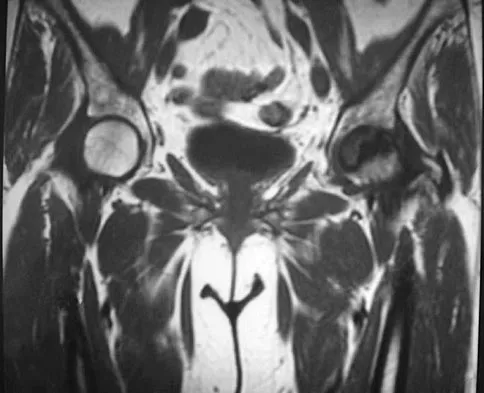

A 62-year-old man has cervical myelopathy with no evidence of cervical radiculopathy. MRI reveals stenosis at C4-5 and C5-6 with severe cord compression. Examination will most likely reveal which of the following findings?

Explanation